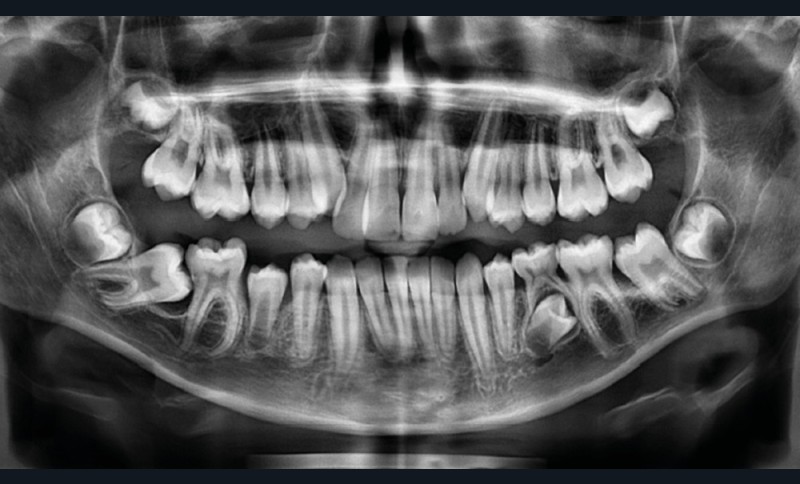

Julien nous consulte à l’âge de 11 ans et 4 mois pour des raisons essentiellement esthétiques, afin d’améliorer l’alignement de ses incisives maxillaires (fig. 1a-d) ; son chirurgien-dentiste l’a toutefois alerté sur un problème d’évolution des 35 et 47, dont l’inclusion a été mise en évidence lors d’un contrôle radiographique (fig. 1e).

L’examen fonctionnel révèle une déglutition dysfonctionnelle qui n’est pas associée à des troubles ventilatoires ni à des problèmes ORL. Cela explique sans doute que l’examen téléradiographique soit quasi normal, puisque la croissance est harmonieuse à la fois dans la dimension sagittale et dans la dimension verticale (fig. 1f).

Il s’agirait donc d’un cas relativement classique de déficit de croissance maxillaire d’origine fonctionnelle, si les inclusions des 35 et 47 ne venaient compliquer la situation…